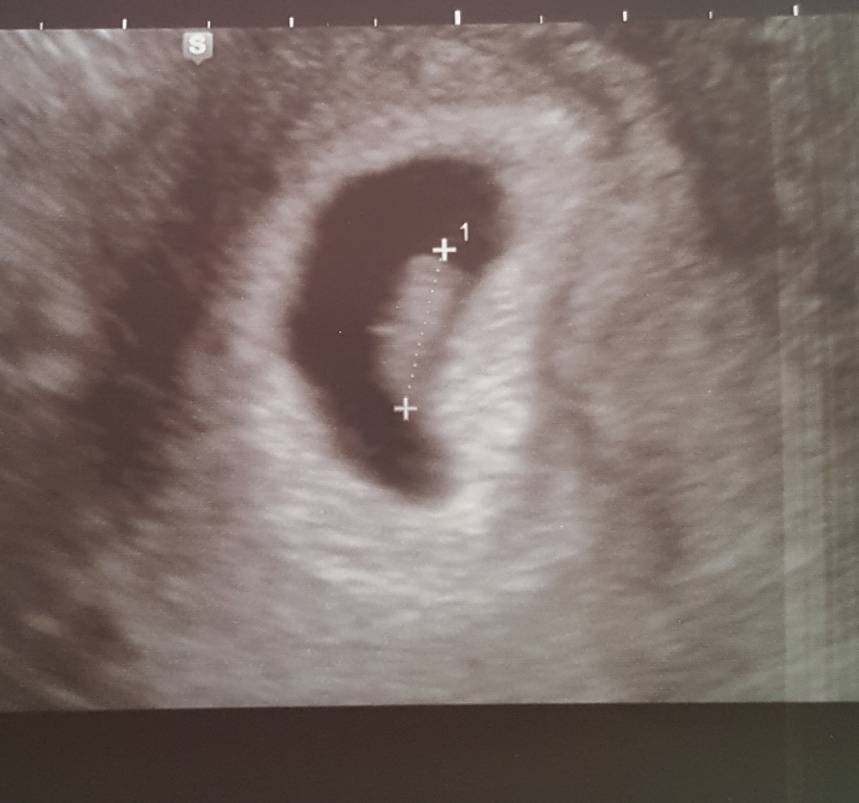

Gdyby którejś z Was zdarzyło się, że nagle piersi przestaną boleć to nie panikujcie tak jak ja dziś w nocy :D obudziłam się o 3.00 i zero bólu... bardzo się zestresowałam, od razu zimne poty i panika, ale na szczęście koło 7 ból wrócił, a na usg (na dziś miałam zaplanowane) wszystko ok. To moje 6 usg w ciągu ostatnich 3 tygodni ze względu na ciągłe plamienia i w końcu takie... uspokajające :) CRL 1 cm, tętno 150 [emoji170]

20191029_150906.jpeg

Gdyby którejś z Was zdarzyło się, że nagle piersi przestaną boleć to nie panikujcie tak jak ja dziś w nocy :D obudziłam się o 3.00 i zero bólu... bardzo się zestresowałam, od razu zimne poty i panika, ale na szczęście koło 7 ból wrócił, a na usg (na dziś miałam zaplanowane) wszystko ok. To moje 6 usg w ciągu ostatnich 3 tygodni ze względu na ciągłe plamienia i w końcu takie... uspokajające :) CRL 1 cm, tętno 150 [emoji170]Zobacz załącznik 1039192